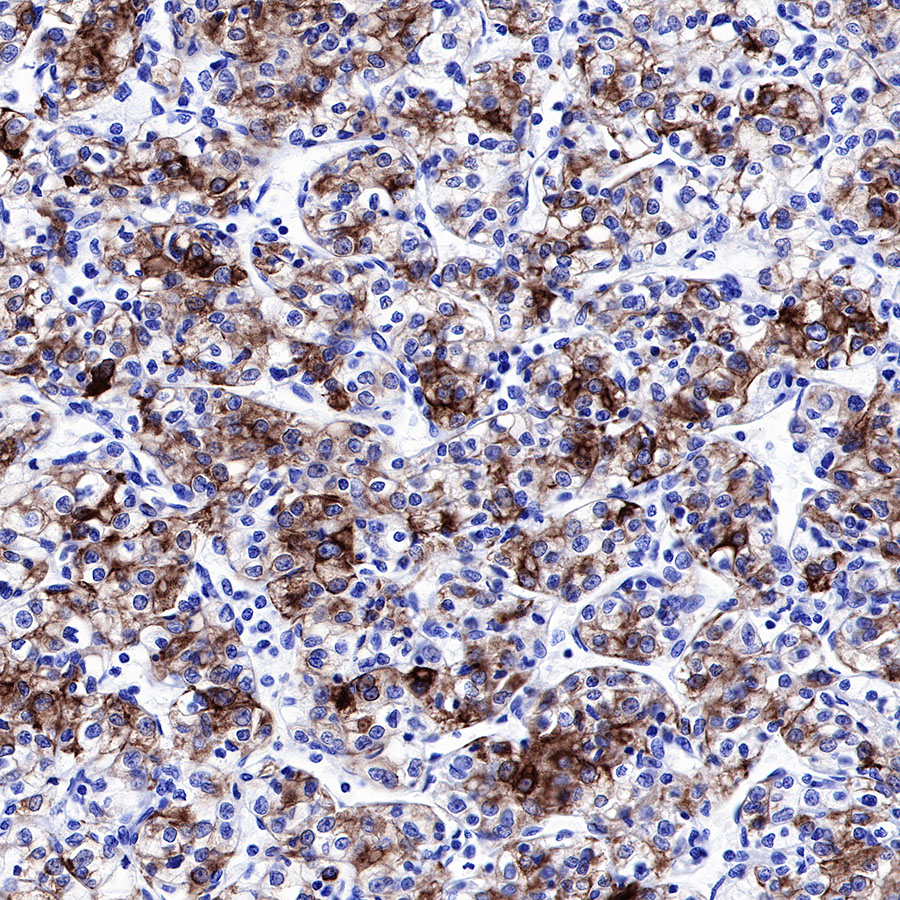

Background

| IHC-P |

1:500-1:2000 |